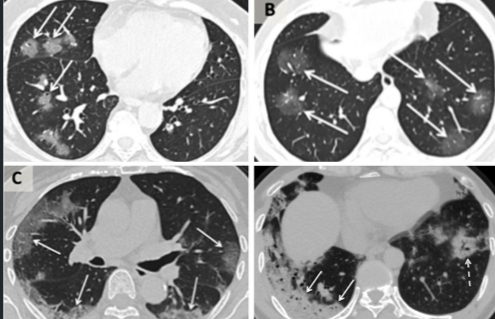

Sebuah studi menemukan bahwa lebih dari 50% pasien yang diteliti, yakni 121 pasien, di Tiongkok, mempunyai hasil CT Scan yang normal pada awal mereka sakit.  Begitu sakitnya mulai parah, CT Scan mulai menunjukan gambar seperti “pecahan kaca buram”, semacam selaput asap yang menutupi beberapa bagian paru-paru. Ini merupakan tanda-tanda infeksi. Selaput ini bisa tersebar di berbagai wilayah paru-paru, dan menebal di wilayah yang parah, sehingga muncul pola “tempelan acak” dalam hasil pemindaian.